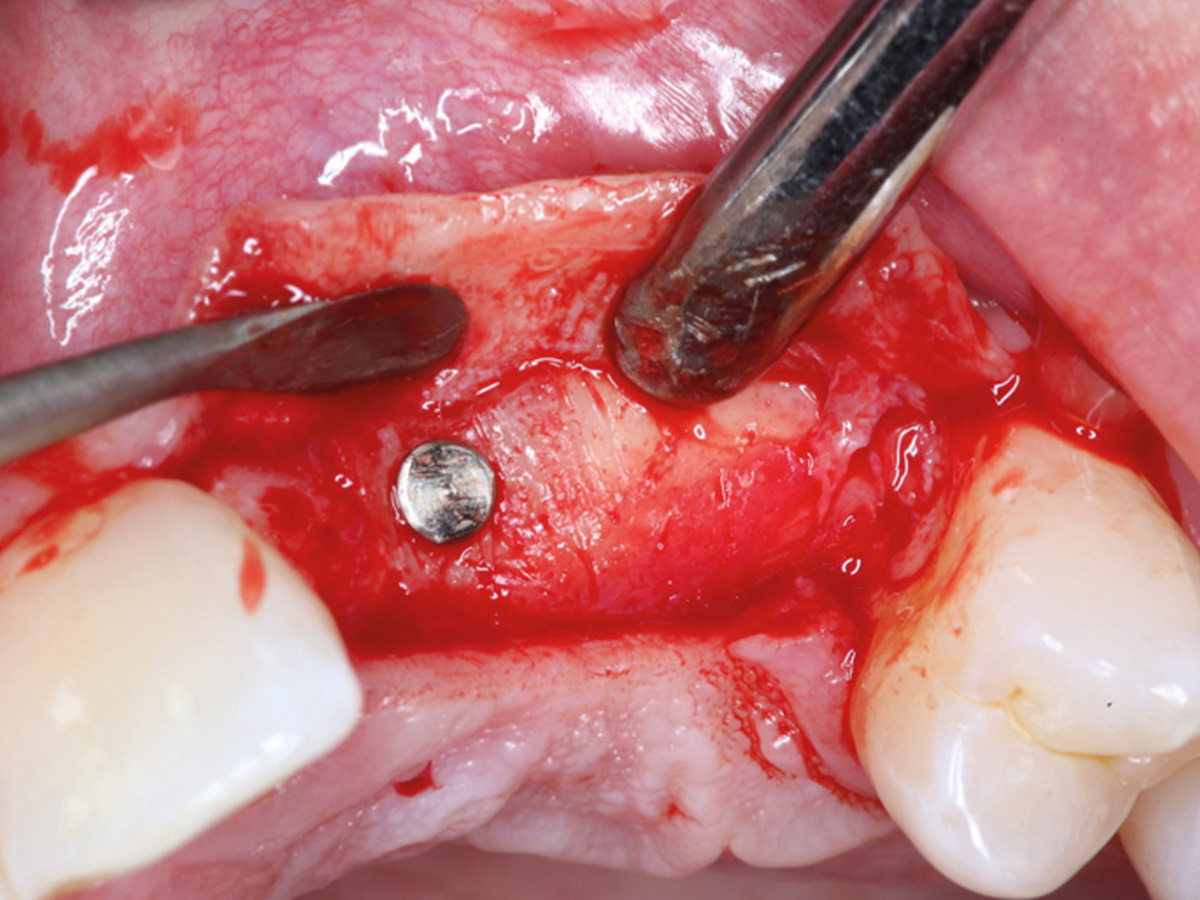

Abbildung 8a

Fixierung der OsteoBiol Lamina mit Pins.